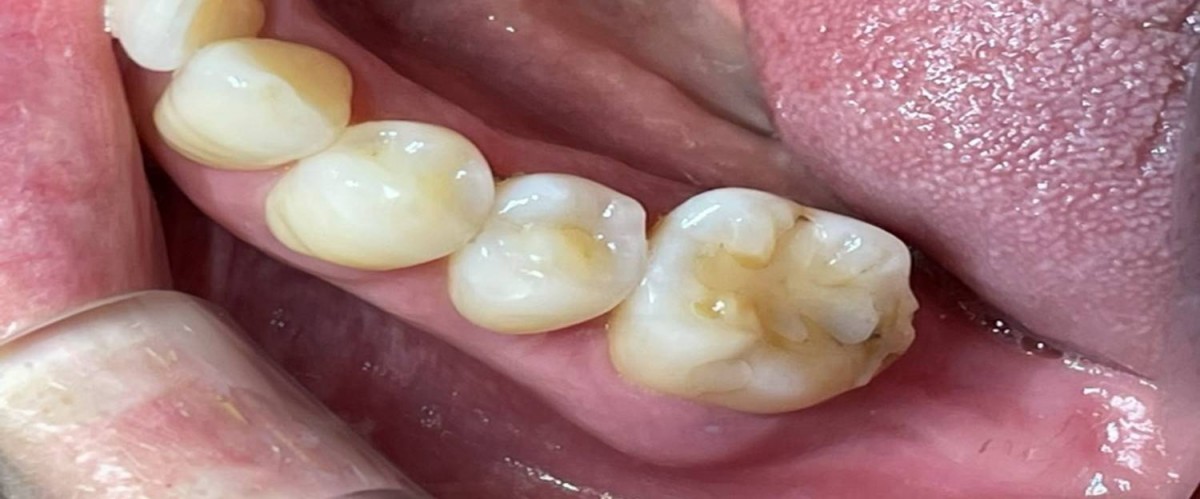

▲Panoramic radiograph after 1 year of the crown delivery.